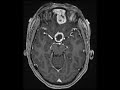

Intracranial Granulomatous Reaction

These images show multiple dural-based rim and solidly enhancing masses along the olfactory groove and frontal cranial fossa with peripheral hemosiderin and areas of central restricted diffusion which could be concerning for abscess formation or recurrence depending on the timeline. There is surrounding T2 FLAIR hyperintensity compatible with vasogenic edema. This patient had previously undergone resection of a planum sphenoidale meningioma and subsequently developed these enhancing collections and masses. These were subsequently debrided and pathology showed them to represent foreign body granulomas which developed in reaction to cotton fibers which is commonly used for hemostasis in neurosurgery.